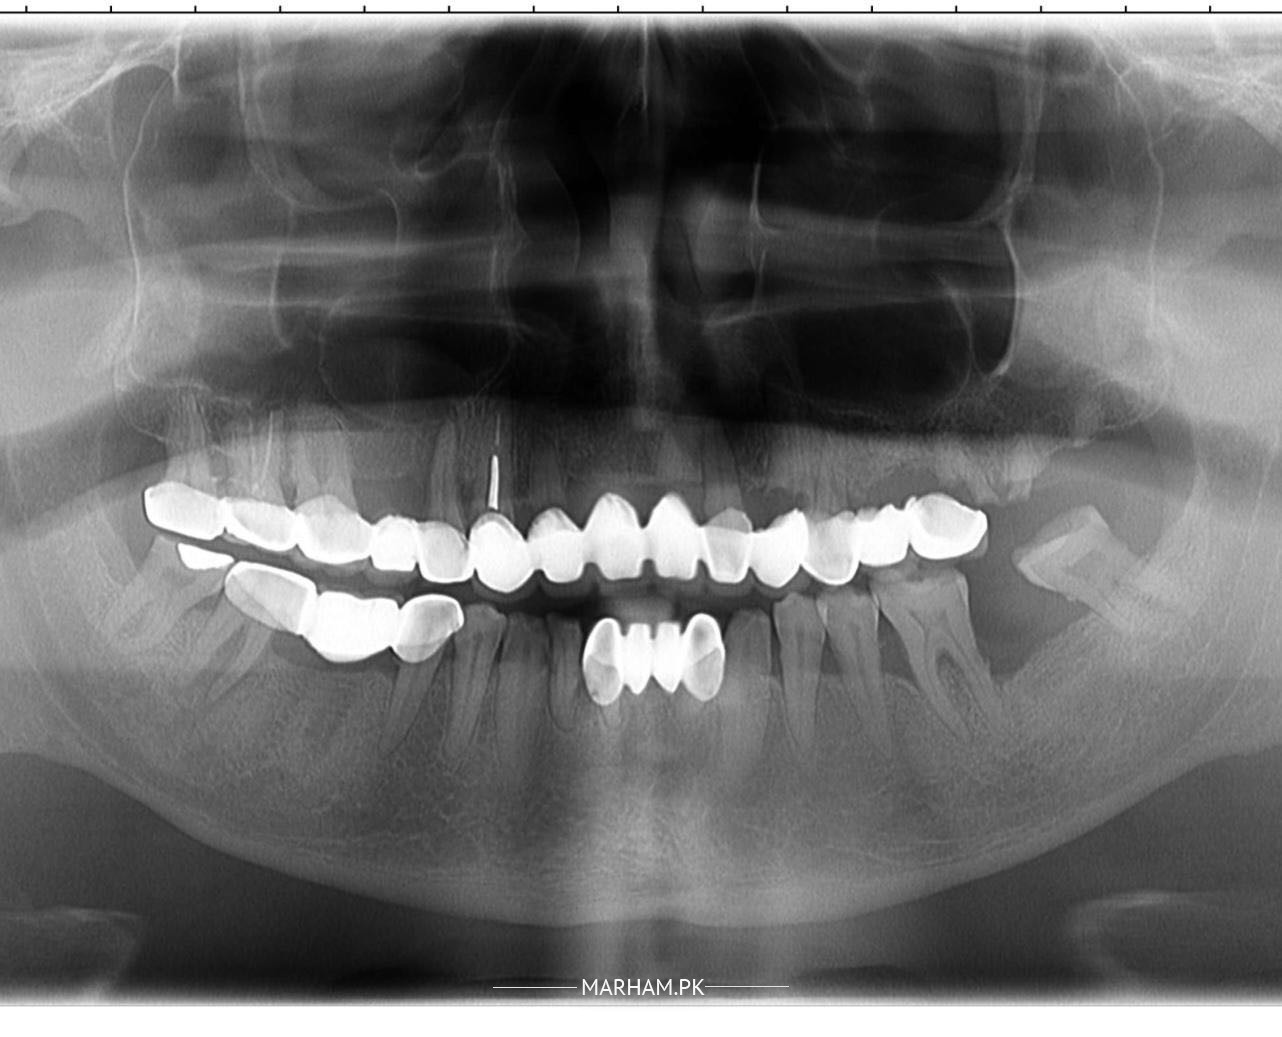

I have got some issues with teeth, some gum issues like gingivitis although some teeth are in good condition. Should all teeth be removed for dental implants or keep the remaining which are comparatively in better condition?

Need further evaluation but however your teeth on the right upper side have very poor prognosis and need to be removed, rest seems restorable we should use a combination of imlants and natural teeth for restoration

why do you have so many crowns ?

you don't need to remove all retained tooth if they are in healthy condition plus why so much bridges? can you show your older xrays before place of these crown and brigdes.